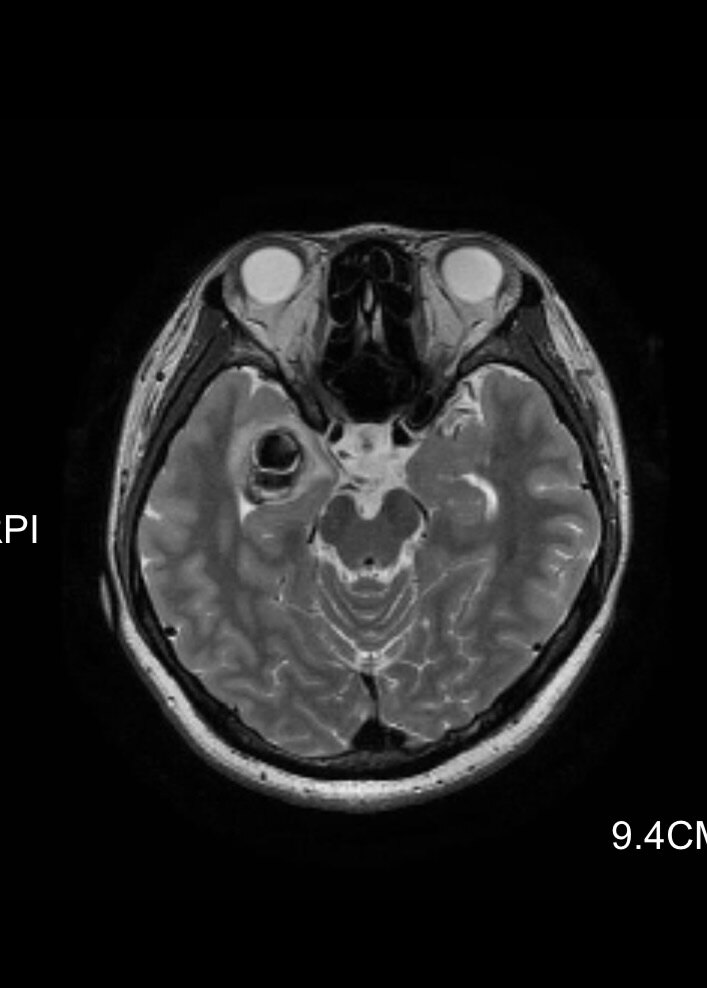

术前提示右颞占位

我们上周有一个24岁的花季女孩,因为突然晕倒发现颅内有一个海绵状血管瘤合并出血。很小的偶然发现的颅内的海绵状血管瘤如果没有症状,很多也可以暂时采取观察的措施就是定期复查头颅磁共振或者CT,不一定要马上手术治疗。但这个女孩发生了晕倒的症状,而且磁共振提示海绵状血管瘤有出血,所以还是强烈建议患者手术治疗。但这个女孩心理上无法接受理发,因为她的头发已经留了很多年,达到了“长发及腰”的水平,而且这个女孩从事舞蹈专业,对外貌要求非常高。所以我们跟女孩仔细沟通过后,没有理发,而是在手术切口上稍微剪掉了一点点头发,切口也是非常的微创,术后女孩恢复的也很快,没有发生感染的情况,术后4天非常满意的出院了。